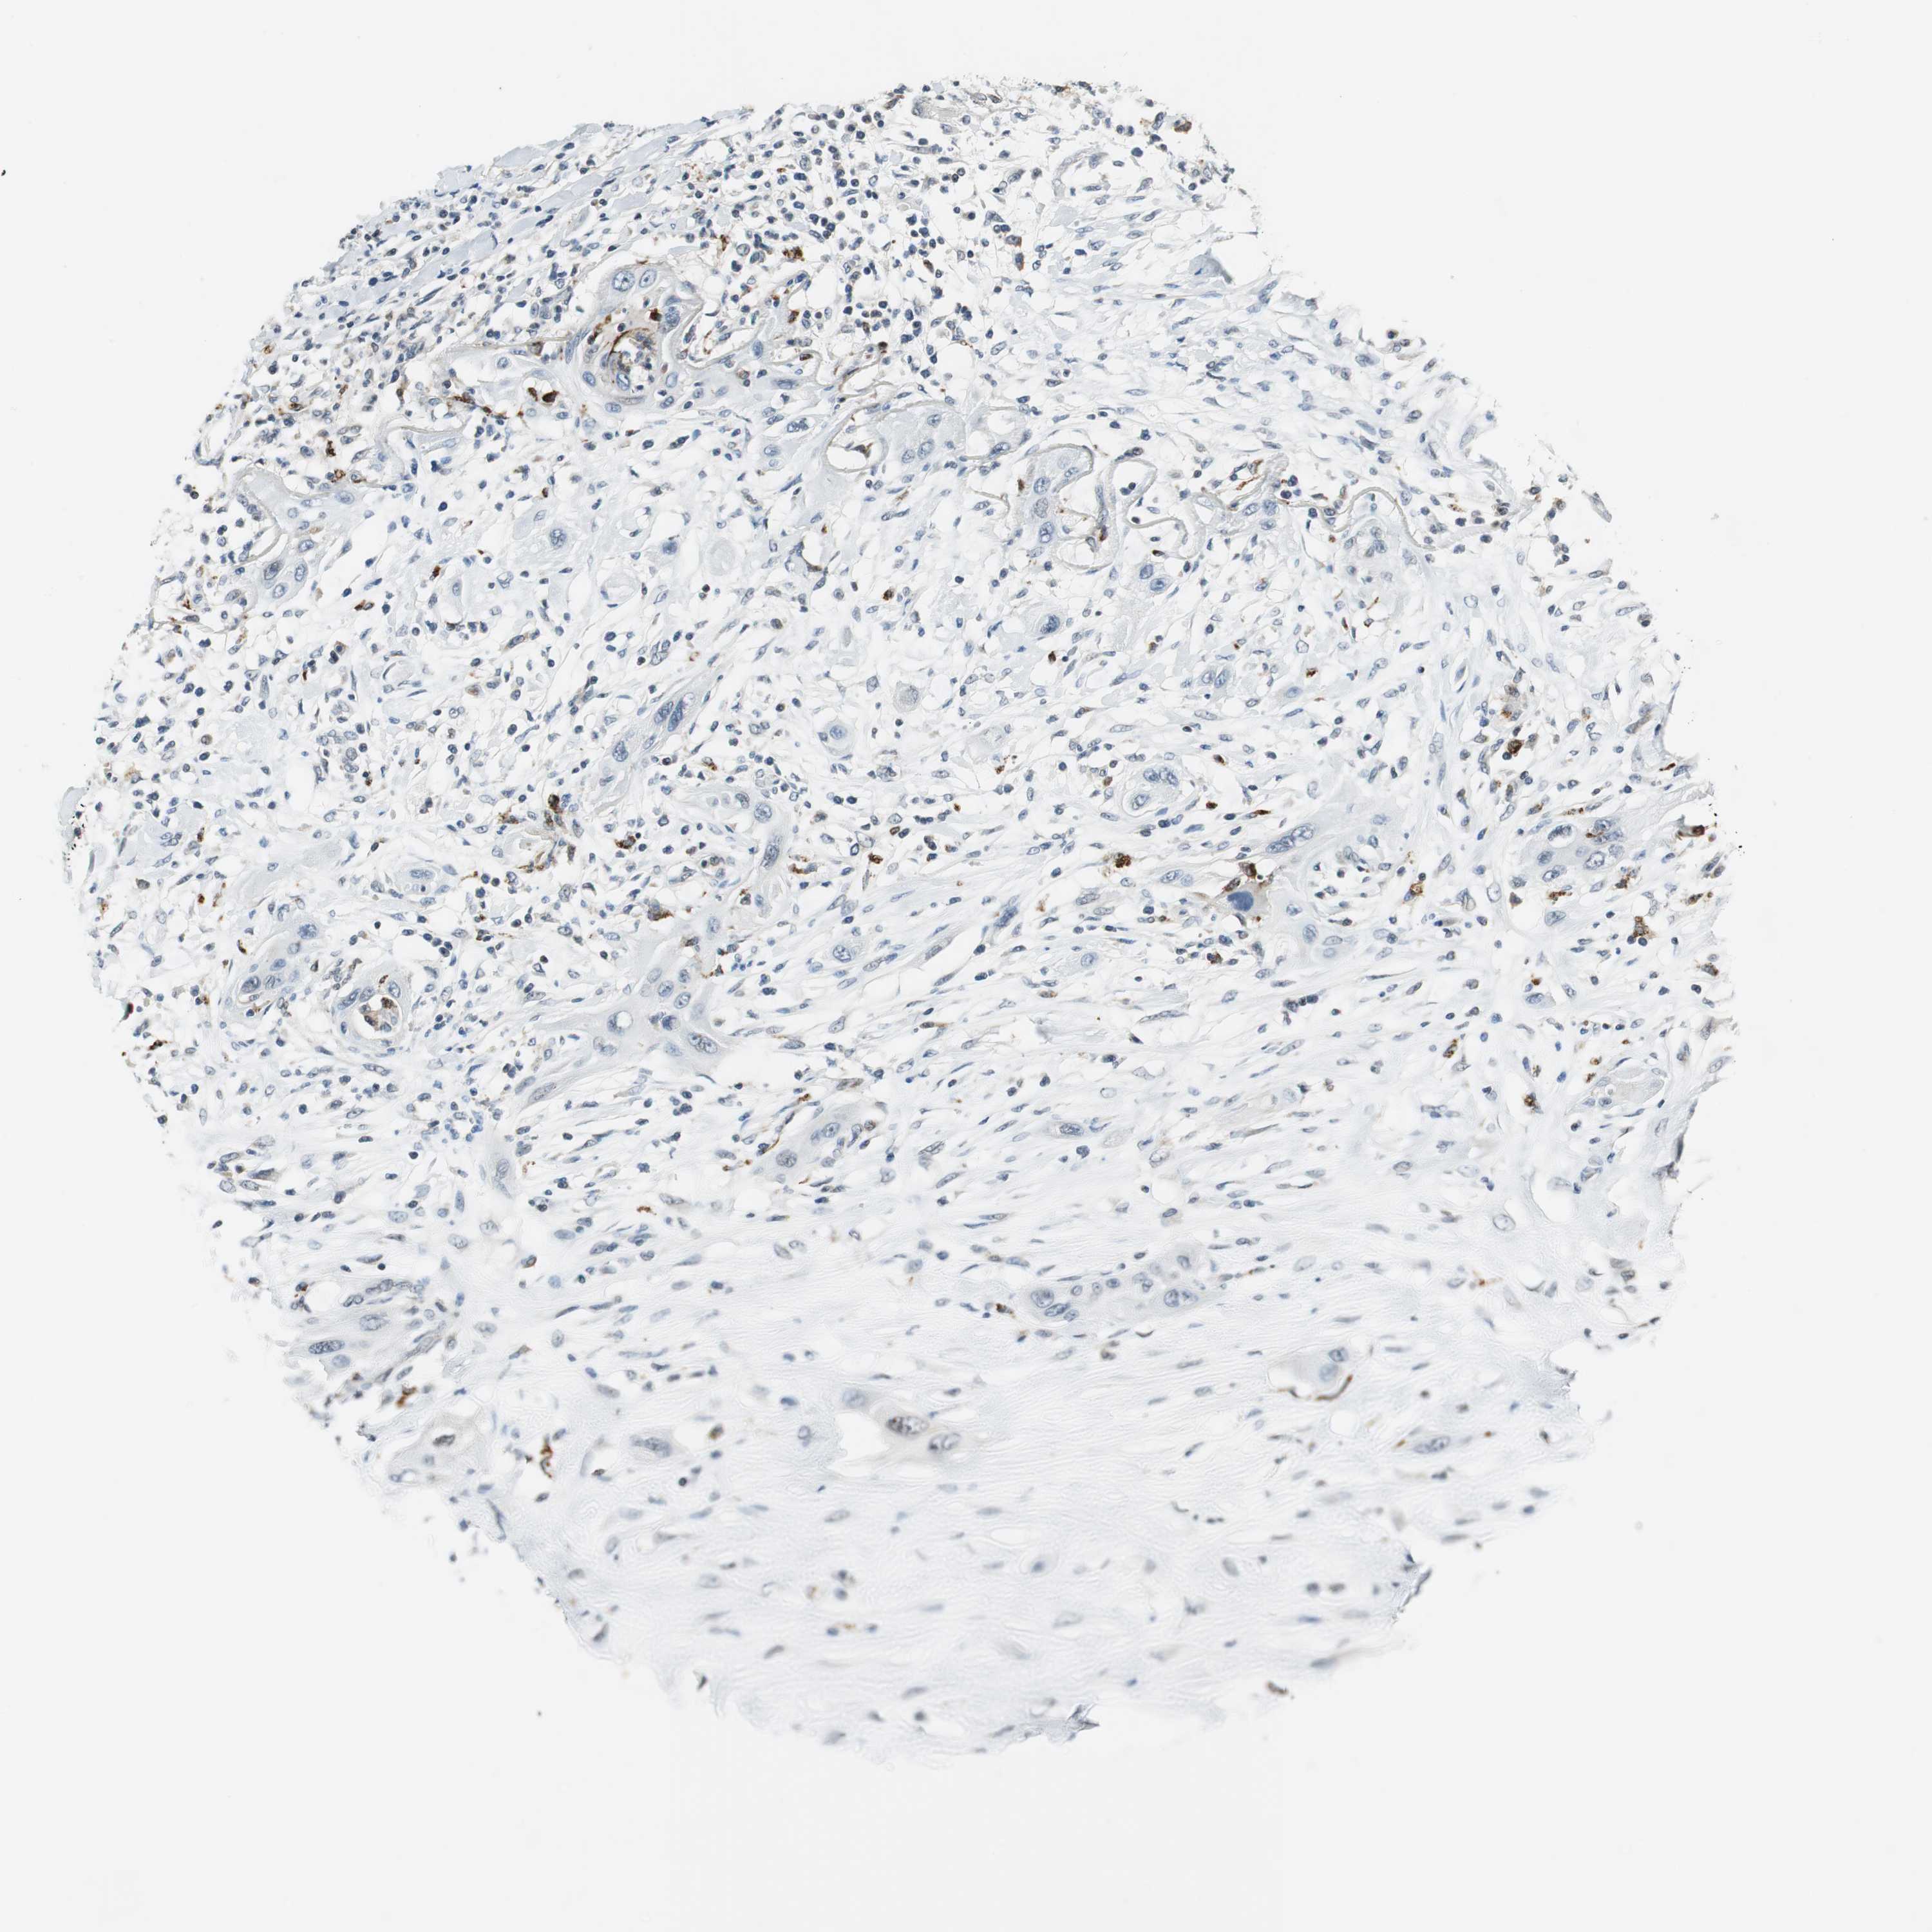

LUNG ADENOCARCINOMA (TCGA) - Interactive survival scatter ploti

The Survival Scatter plot shows the clinical status (i.e. dead or alive) for all individuals in the patient cohort, based on the same data that underlies the corresponding Kaplan-Meier plots. Patients that are alive at last time for follow-up are shown in blue and patients who have died during the study are shown in red.

The x-axis shows the expression levels (FPKM) of the investigated gene in the tumor tissue at the time of diagnosis. The y-axis shows the follow-up time after diagnosis (years). Both axes are complimented with kernel density curves demonstrating the data density over the axes. The top density plot shows the expression levels (FPKM) distribution among dead (red) and alive patients (blue). The right density plot shows the data density of the survived years of dead patients with high and low expression levels respectively, stratified using the cutoff indicated by the vertical dashed line through the Survival Scatter plot. This cutoff is automatically defined based on the FPKM cutoff that minimizes the p-score. The cutoff can be changed by dragging the vertical line or by entering a cutoff value in the square labeled "Current cut-off".

Under the Survival Scatter plot the p-score landscape (black curve; left axis) is shown together with dead median separation (red curve; right axis). Dead median separation is the difference in median mRNA expression between patients who have died with high and low expression, respectively. It is calculated as follows: median FPKM expression of dead patients with high expression - median FPKM expression of dead patients with low expression. This is intended to aid the user in visually exploring custom cutoffs and the associated p-scores and dead median separation.

Individual patient data is displayed and can be filtered by clicking on one or more of the category buttons on the top of the page. Categories describing expression level and patient information include: high, low, alive, dead, female, male and tumor stages. The scale of the x-axis can be toggled between linear and log-scale by clicking on the "x log" button. Mouse-over function shows TCGA ID, patient information and mRNA expression (FPKM) for each patient.

& Survival analysisi

Kaplan-Meier plots summarize results from analysis of correlation between mRNA expression level and patient survival. Patients were divided based on level of expression into one of the two groups "low" (under cut off) or "high" (over cut off). X-axis shows time for survival (years) and y-axis shows the probability of survival, where 1.0 corresponds to 100 percent.

NCK1 is not prognostic in Lung Adenocarcinoma (TCGA)

: 19.49